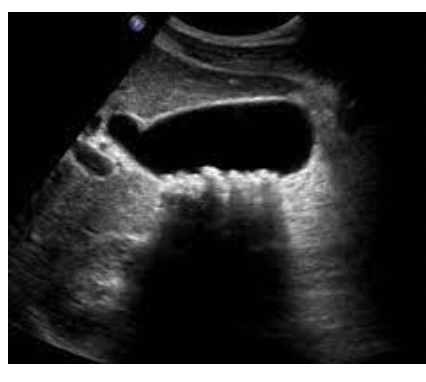

What pathology is in the image below ?

Cholelithiasis/Gallstones - Increased wall thickness, internal reflections, mobile, hyperechoic